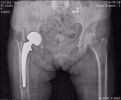

【疑难病例】骨二科采用一期骨水泥间置器植入技术翻修髋关节

人工髋关节置换术现今已成为骨科治疗严重髋关节疾患的标准手术之一。随着外科手术技术的提高,材料技术和加工技术的进步,髋关节置换手术术后感染的发生率逐年降低,但术后感染仍是无法避免的并发症。关节置换术后感染的治疗包括单纯应用抗生素、保留假体的清...